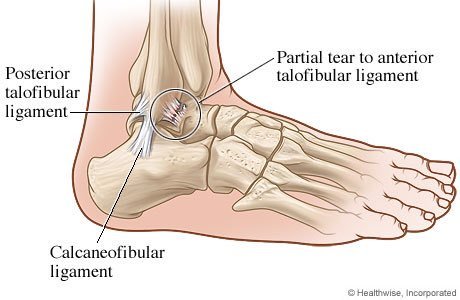

When there is a lateral ankle sprain, which ligaments are affected?

1. Anterior/posterior talofibular ligaments

2. Calcaneofibular ligaments

1. Pain

2. Bruising

3. Mild/moderate tenderness